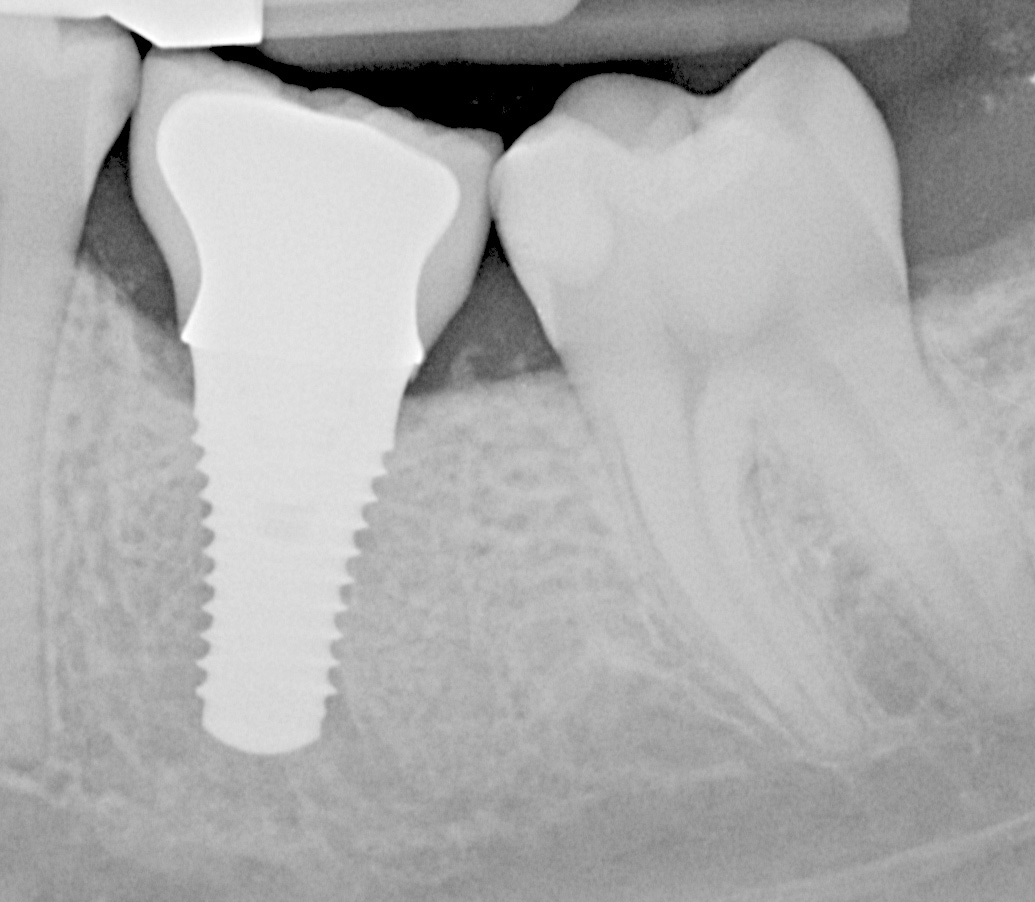

Fig 5. Radiograph of a mandibular right first molar implant in a 31-year-old woman taken 1 year after placement. No bone loss beyond physiologic remodeling has occurred; there is a suggestion of possible cement at the distal.

Figure 5